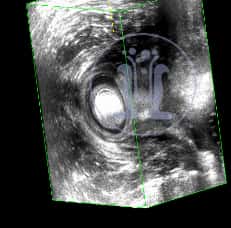

Ασθενής γυναίκα με φλεγμονή στο πεπτικό, προσέρχεται με αδυναμία στην συγκράτηση των κοπράνων. Στο ιστορικό της αναφέρει εγχείρηση με την μέθοδο του Ιπποκράτη. Ανευρίσκονται μετεγχειρητικές αλλοιώσεις του έξω σφιγκτήρα.